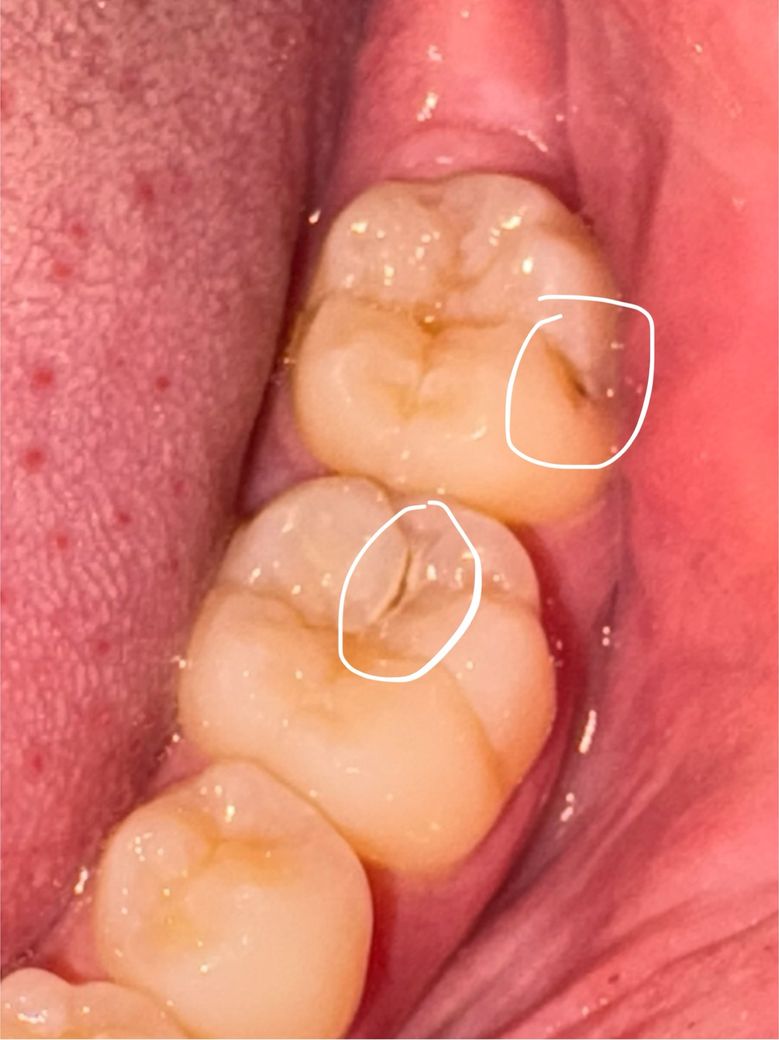

의사 선생님들 충치 관련 질문이 있습니다

질문이 3개가 있습니다 충치인거 같은데 레진으로 어금니를 때워도 될까요? 이상태에서 2개월정도 치과를 안갈시 크게 문제가 될까요? 일단 치료를 받아야하는걸까요? 답변 해주시면 감사하겠습니다

• 1번 째 사진

사진으로 봤을 경우에는 간단하게 레진으로 치료를 할 수 있을 것으로 생각됩니다. 채 내부에 충치로 인한 공동의 형성되어 있기 때문에 치료를 하지 않으면 해당 부위에 이물질이 들어가게 되어 충치가 더 진행될 수 있습니다.

사진에 보이는 충치가 2주 만에 크게 진행되거나 그렇진 않을꺼니 2주뒤까지 관리를 잘하시고 치료를 받으시면될것같습니다.

충치가 깊게 진행이 되고 있으므로 2개월동안 방치하지 마시고 치과 가보시는 것이 좋습니다

질문이 3개가 있습니다 충치인거 같은데 레진으로 어금니를 때워도 될까요? 이상태에서 2개월정도 치과를 안갈시 크게 문제가 될까요? 일단 치료를 받아야하는걸까요? 답변 해주시면 감사하겠습니다 -> 이정도면 바로 치료 필요한 충치상태입니다 레진으로 시도해봅니댜